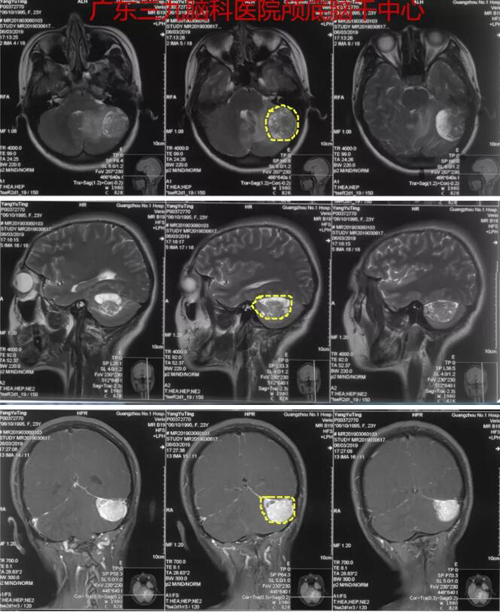

杨某,女,23岁,因“乳腺癌术后2年,间断头晕4个月”于2019年3月8日入院。患者无明显诱因出现眩晕呕吐,外院检查头颅MR示左侧桥小脑角区占位,为进一步诊治,转入广东三九脑科医院神经外一科。完善相关检查后3月12日全麻下为患者行“左侧桥小脑角区占位性病变切除术”,术程顺利,病理报告示: (左侧桥小脑区)孤立性纤维性肿瘤/血管周细胞瘤。

图1:术前MR示左侧小脑占位性病变,与天幕、乙状窦关系密切,结合病史(乳腺癌术后2年),考虑转移瘤可能性大,不除外脑膜瘤可能。

图2:术后CT及MR示肿瘤全切除